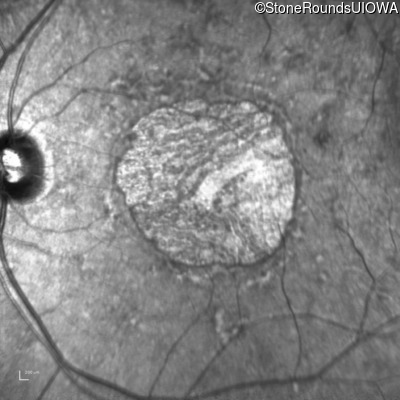

Fluorescein Angiography - Left - 20/30 +1

Exemplar